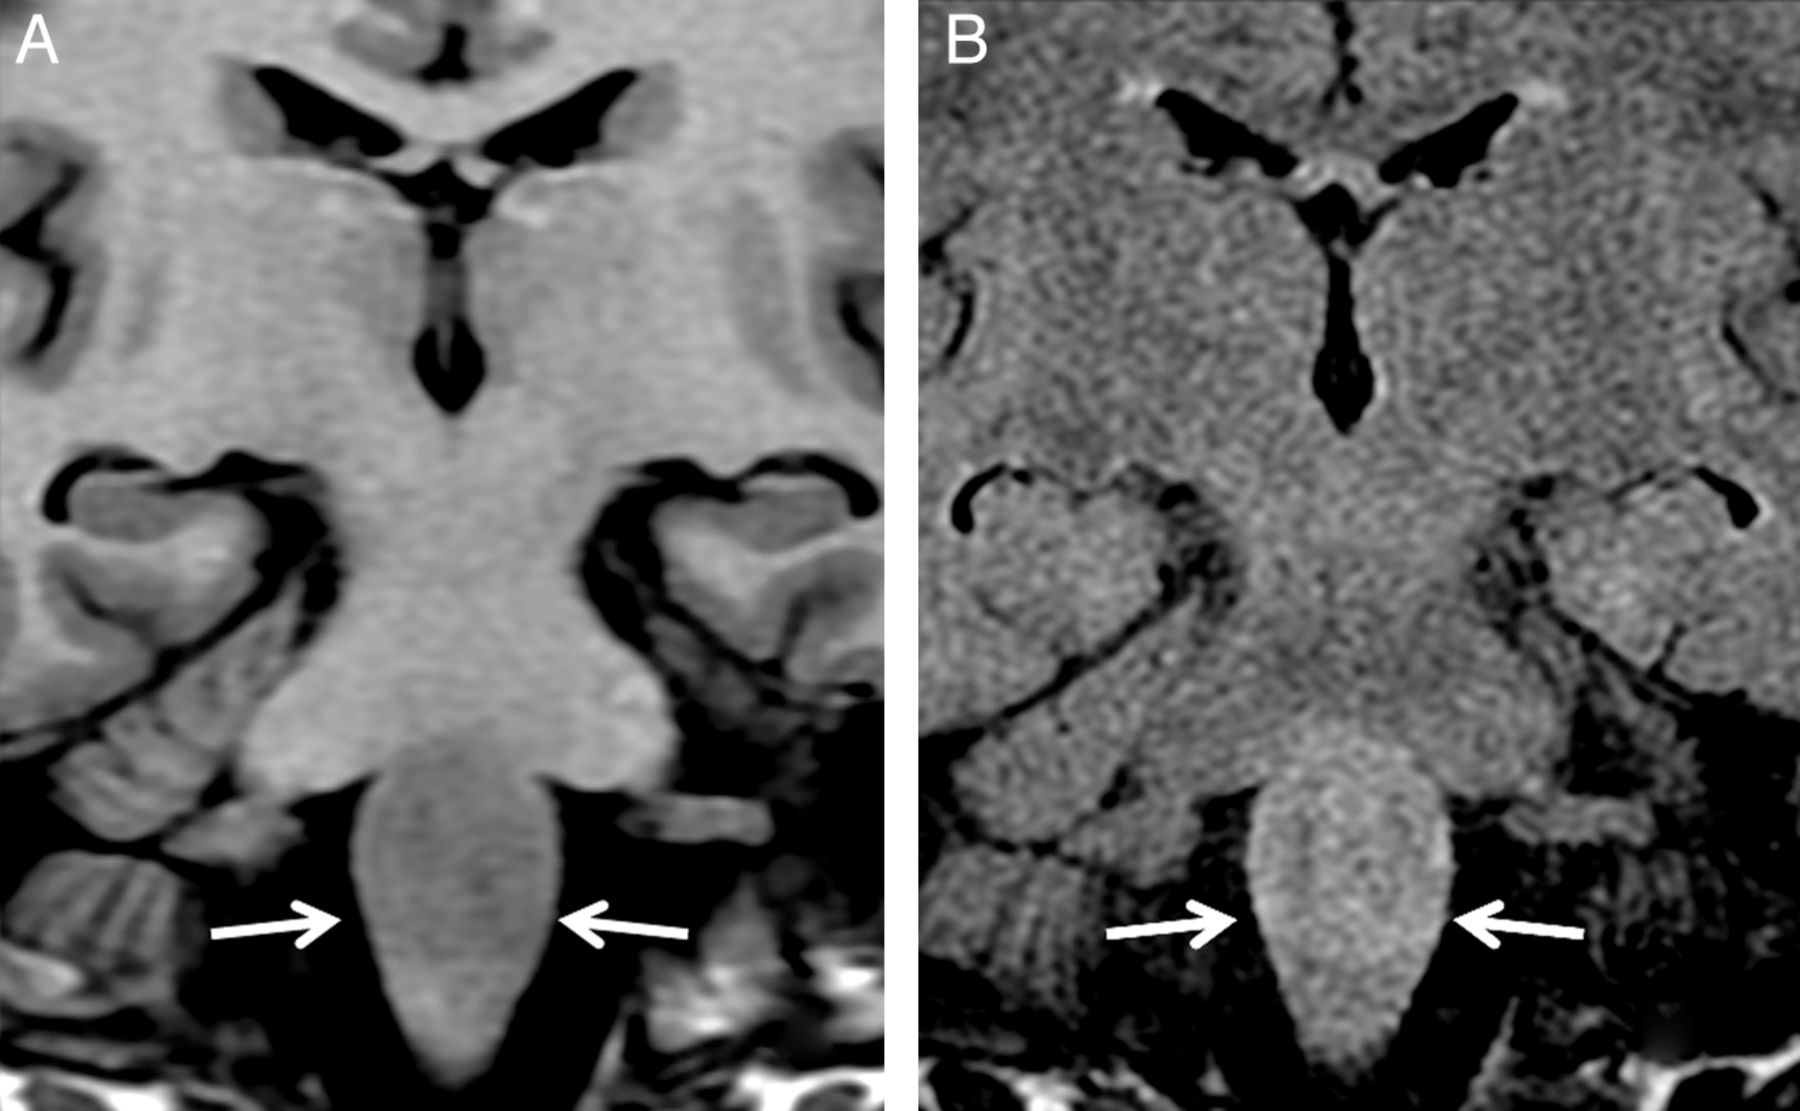

Case 4. Coronal T1-weighted image (A) shows hypointensity involving the medulla oblongata (arrows), and the coronal FLAIR image shows hyperintensity (arrows, B).